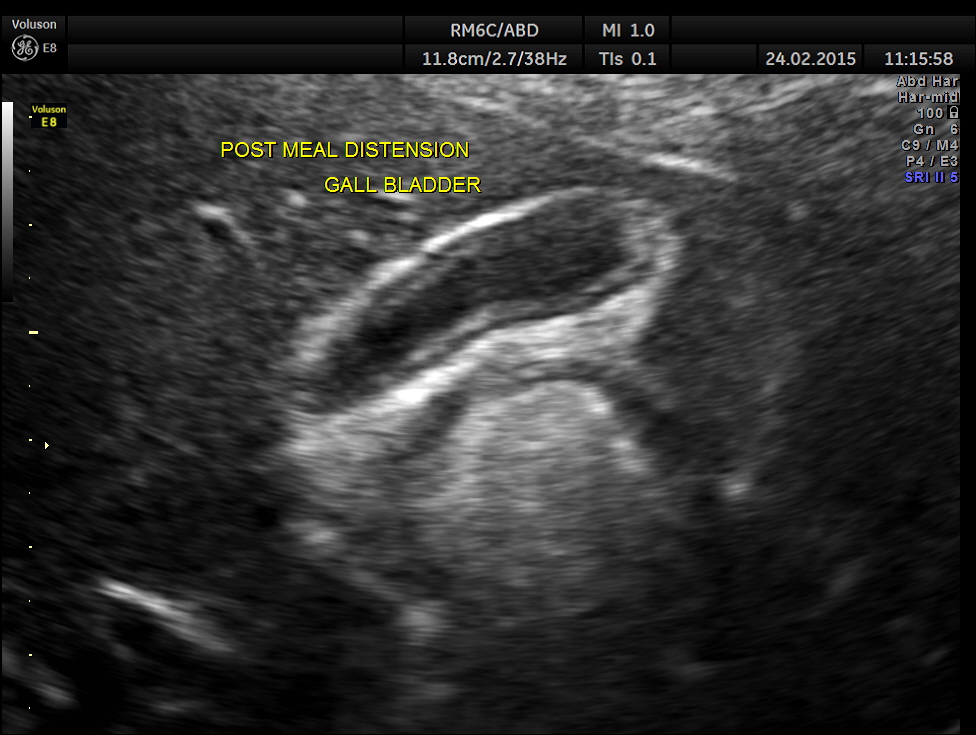

The patient was asked to take a fatty meal and report again and this was seen.The gall bladder has started to be filled up and was showing distension , contrary to what happens in a normal person.

2 hours after the meal the gall bladder was still distended and no gallstone was visualised .